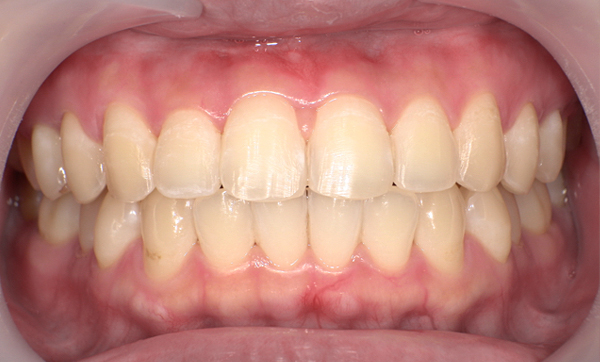

症例_001 前歯「八の字/V字型」症例

治療期間:17ヶ月金額:54万円+税20代女性八の字/V字型

| Before | After |